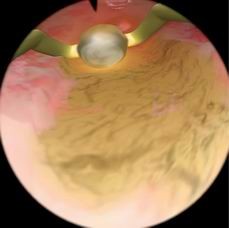

子宫内膜去除模块

可练习如何使用滚球电极,进行子宫内膜去除术的操作

Essure植入体避孕模块

用于培训学员练习如何安置永久性节育装置